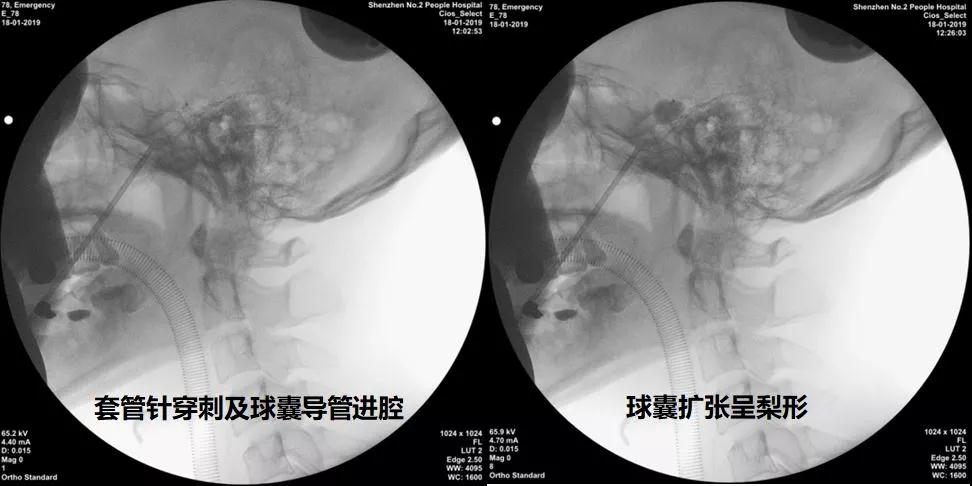

经过细致、严谨的术前准备后,蔡晓东主任团队在三叉神经痛专家(已完成三叉神经半月节阻滞术上千例)付友增教授指导下于2019年01月18日上午顺利完成了ROSA机器人辅助下经皮穿刺三叉神经半月节微球囊压迫手术(PBC),术中球囊充盈呈标准梨形,球囊充盈体积为0.6ml,压迫时间为90秒。手术过程顺利,从右侧面部皮肤穿刺进针,到穿刺卵圆孔到位,到最后球囊压迫,只需10余分钟便完成手术。

(经皮球囊压迫治疗三叉神经痛步骤)